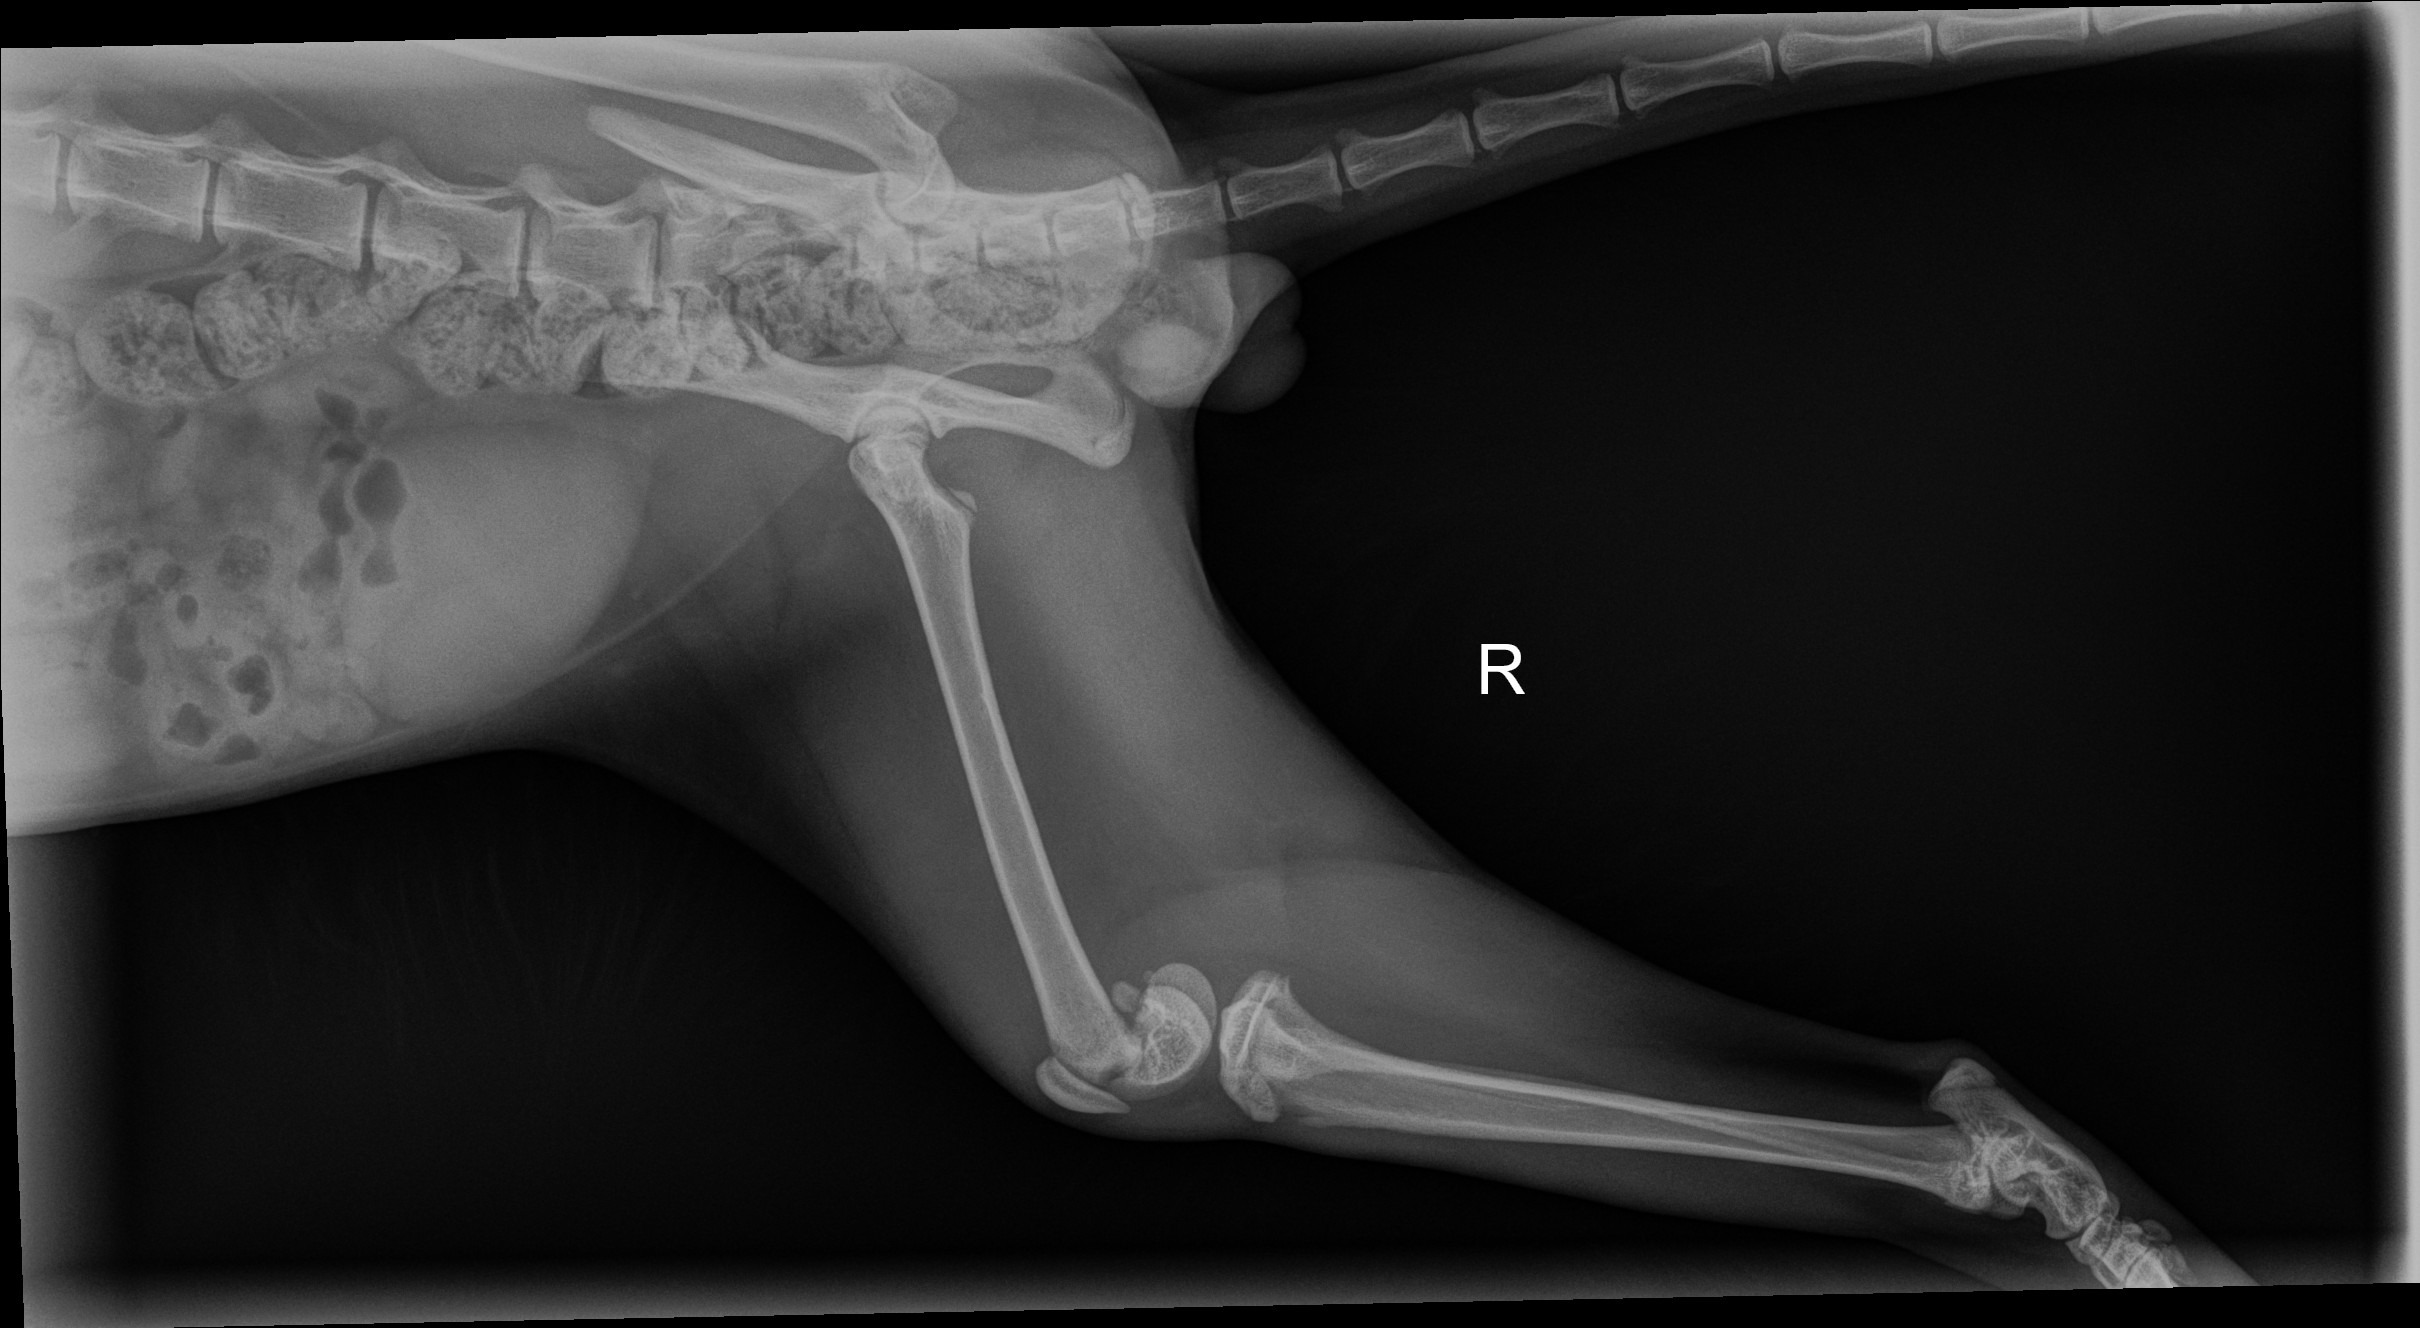

What happened to Teddy's leg? We may never know, but a trip to the vet for x-rays gave us some more information: his femur is broken, and it will require surgical intervention. Given the location of the break at the joint, Teddy might need an amputation. He is only a few months old; this should never have been his fate, but here we are.